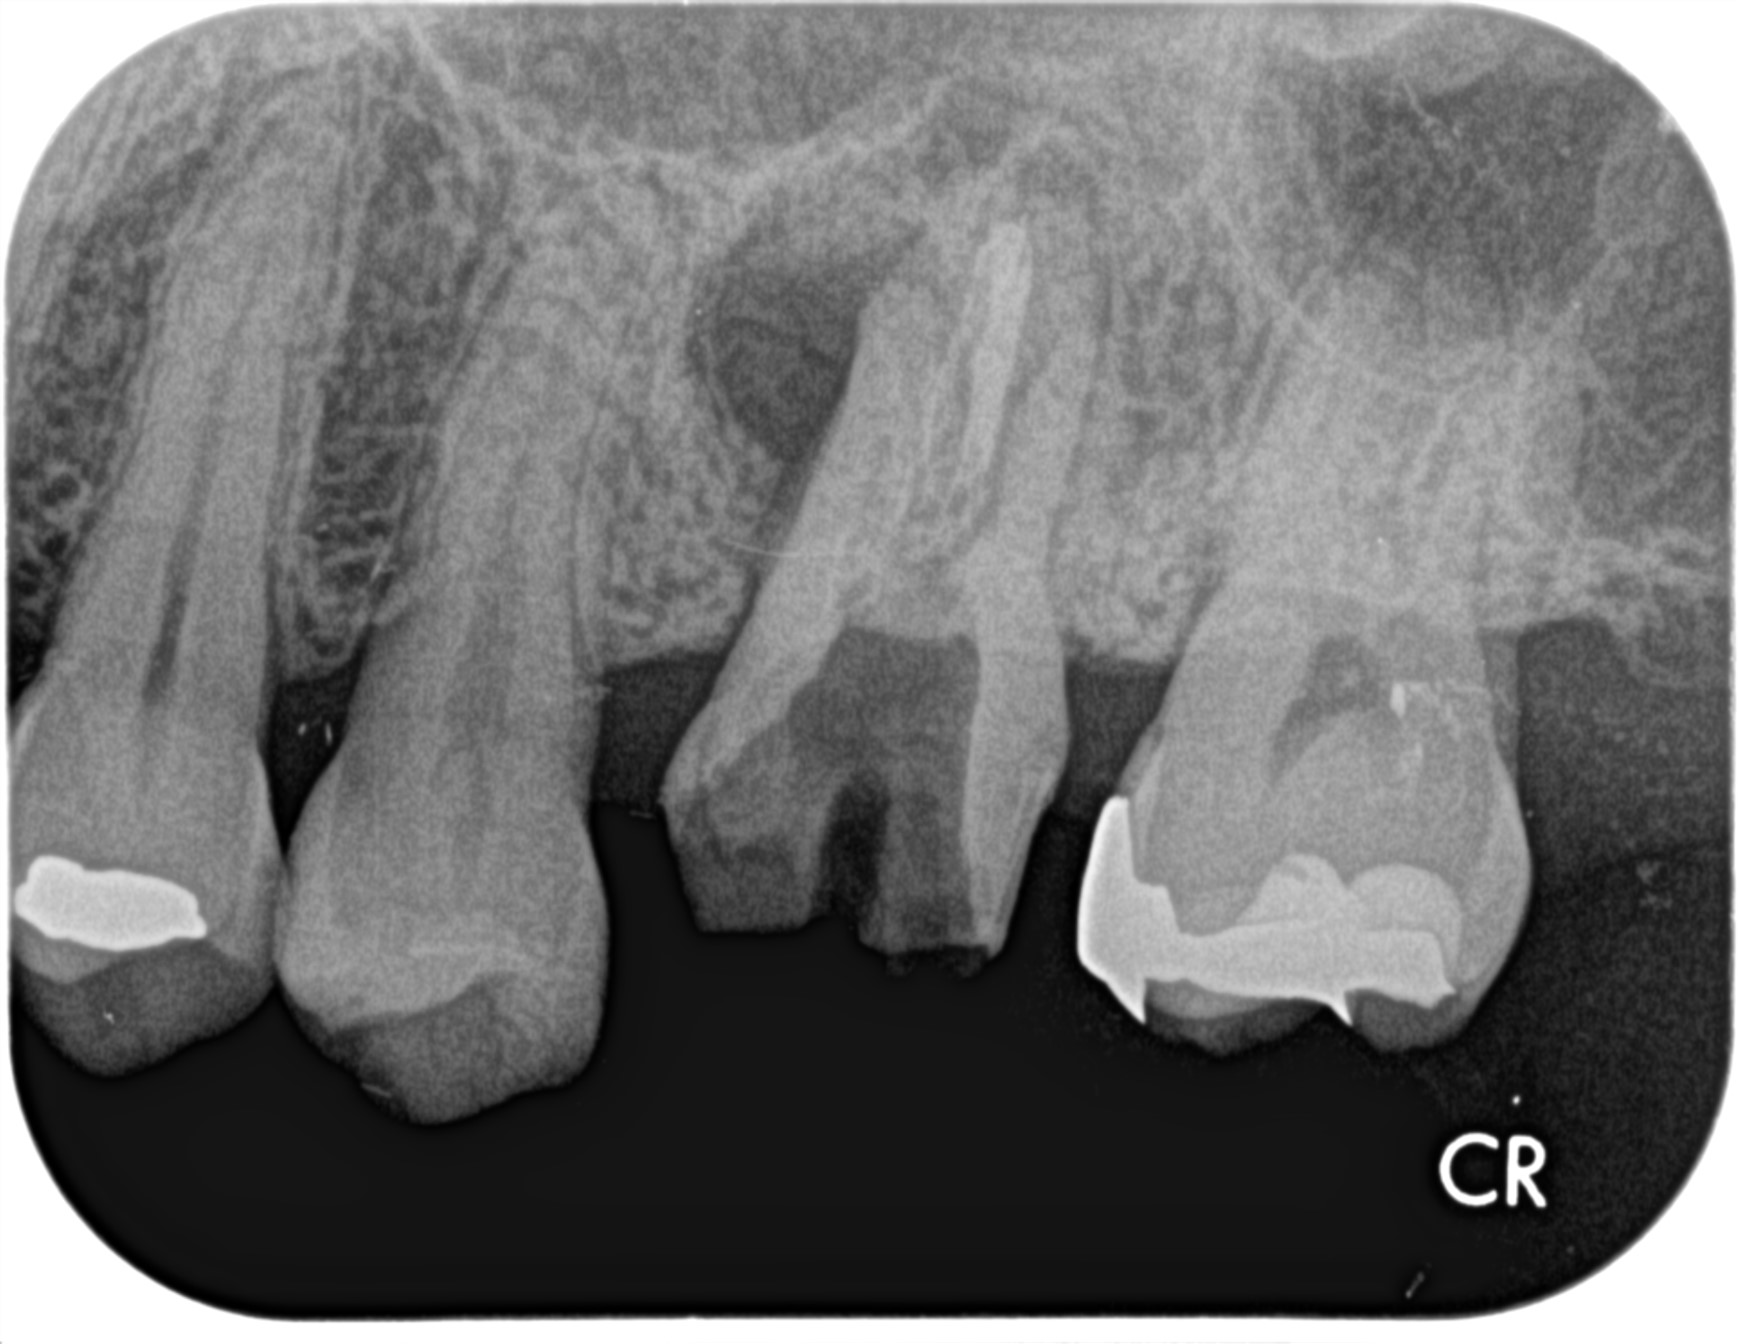

治療前